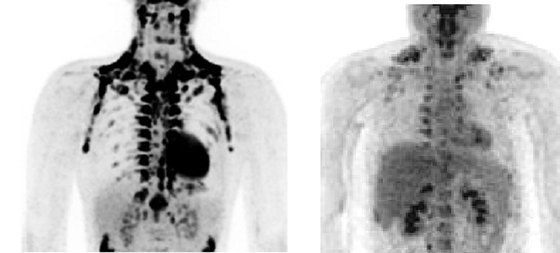

Imágenes de PET-TAC de grasa parda / W. D. VAN MARKEN LICHTENBELT

Ni dieta de la alcachofa, ni sesiones extenuantes de gimnasio, ni balón intragástrico. Por extraño que parezca, la grasa podría acabar siendo la mayor aliada en la lucha contra la obesidad. Además del tejido adiposo malo, de tono blanquecino o amarillento, responsable de los michelines y el sobrepeso, existe otra grasa buena que quema calorías.